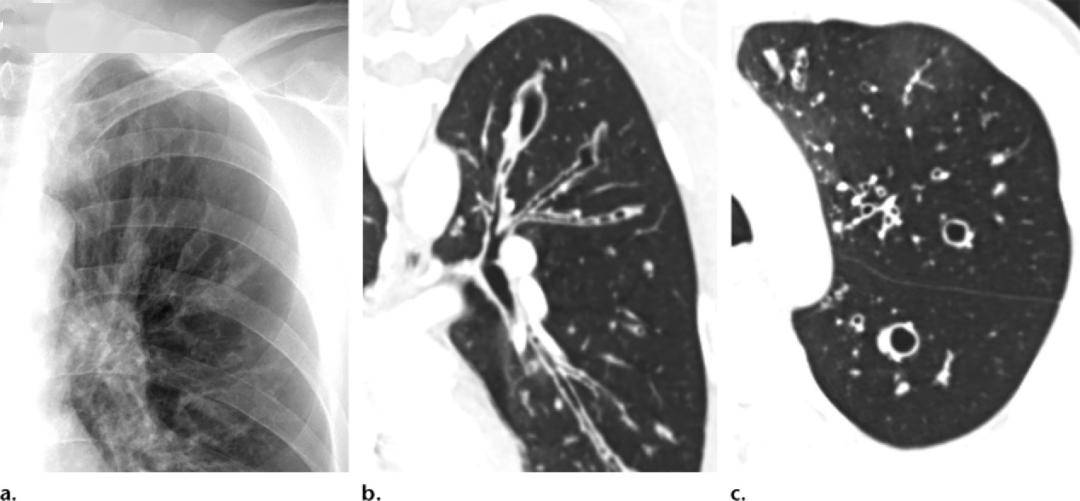

冠状面:支气管扩张(箭头)伴感染(圆圈)结果胸部ct做下来,显示小伙子的